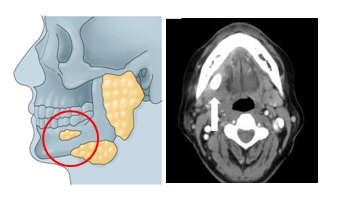

4. 침샘종양

침샘종양은 침을 만드는 타액선에 발생하는 종양을 말하는데요. 이 곳에는 귀밑샘, 턱 밑선 및 설하선의 큰 침샘과 구강 내의 작은 타액선이 있습니다.

침샘종양의 80%~90%는 귀밑샘과 턱밑에 발생하기 때문에 귀밑과 턱밑 종양의 대표적인 질환인데요. 종양에는 양성종양과 악성종양이 있습니다.

침생종양의 주요 증상은 귀 아래나 턱밑 멍울과 함께 붓기가 생기는데요. 멍울이 갑자기 커지거나 통증을 동반하는 경우는 악성일 가능성이 있습니다.

또한 안면에 신경이 마비되는 증상이 동반하는 경우는 특히 악성 종양일 가능성이 매우 높은데요. 때로는 종양이 경부 림프절로 전이될 수 있으며, 이 경우는 경부의 멍울도 나타납니다.